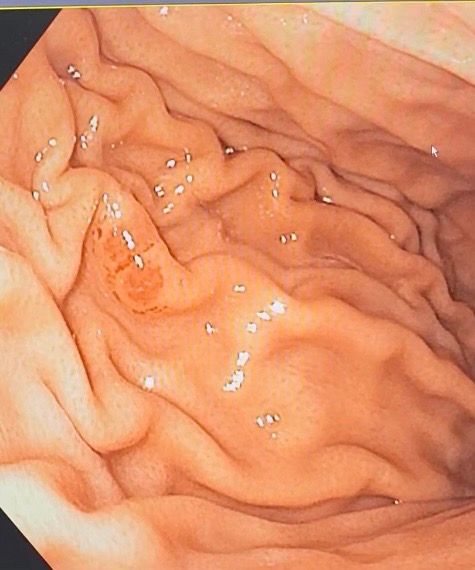

최근에 위내시경을 받았는데 위 점막에 붉은 동그라미가 있더라구요. 담당선생님께서는 괜찮은거 같다하시며 조직검사 안해주셨는데 1년반전에 내시경에 없던 것이 여서 걱정이에요. 그리고 한장 더 올린 사진도 봐주세요. 이게 뭘까요? 괜찮은걸까요? 다시 위내시경 해봐야할까요?

내시경 검사를 시행한 의사에게 설명을 듣는 것이 가장 정확하겠으나 같이 올려주신 사진으로 미루어 내시경 검사 중 위에 고여 있는 물이나 점액을 제거 시 점막이 같이 흡인되어 일시적으로 반점처럼 생기는 경우가 있겠고 만성 위염과 연관된 변화의 가능성도 생각됩니다.

설명 들으신 바와 같이 당장 악성 질환이 의심되는 소견은 아니므로 너무 걱정하진 마시고 걱정된다면 3-6개월 후 재검사를 받아보기 바랍니다.